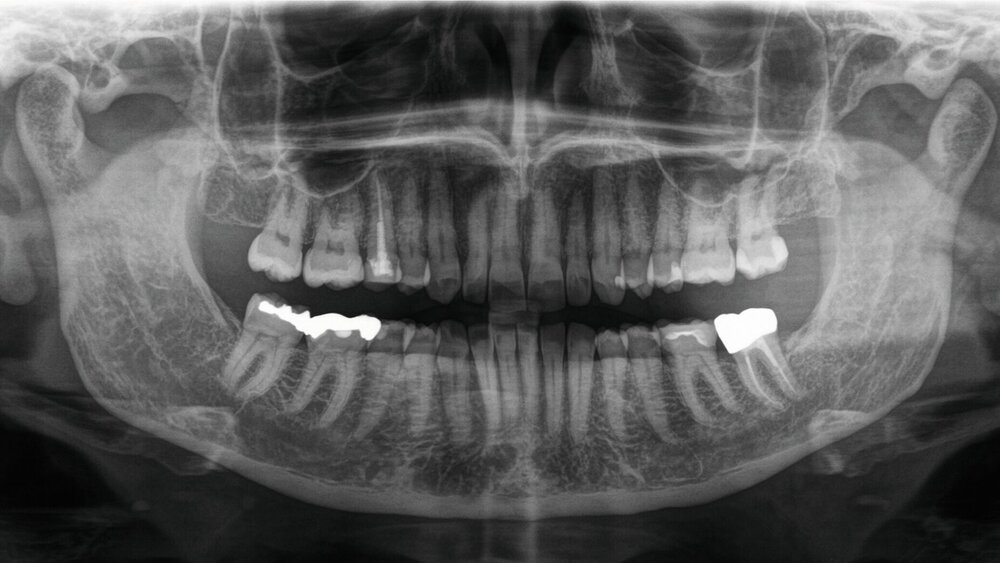

In der zweidimensionalen Bildgebung mittels Orthopantomogramm zeigten sich keine intraossären Raumforderungen im Bereich des N. alveolaris inferior oder des N. mentalis. Die Knochenbinnenstruktur der Unterkieferspongiosa zeigte sich regelrecht. Es lagen keine Hinweise für einen dentogenen Fokus oder allgemein entzündliche Prozesse vor.

Wie erwähnt sind die hauptsächlich auftretenden initialen Symptome Sehstörungen durch eine entzündliche Affektion des N. opticus. Erschwerend in der klinischen Ersteinschätzung kamen bei der hier beschriebenen Patientin die angegebenen CMD-Symptome hinzu. Auch mit diesem multifaktoriellen Krankheitsbild können infolge der Fehl- und Überbelastung der muskulären Strukturen Hyper-, Par- und Anästhesien vergesellschaftet sein. Die genauen Mechanismen scheinen dabei jedoch nicht eindeutig bekannt zu sein, so dass bei entsprechenden Symptomen immer auch differenzialdiagnostisch vorgegangen werden sollte. So werden neben der klassischen, zweidimensionalen Röntgenaufnahme mittels Orthopantomogramm auch dreidimensionale bildgebende Verfahren empfohlen. Dabei zielt eine Computertomografie vor allem auf die Beurteilung des intramandibulären Verlaufs des N. alveolaris inferior und der knöchernen Strukturen ab, während die Magnetresonanztomografie Veränderungen innerhalb des zentralen Nervensystems detektieren kann. Bei entsprechendem Nachweis oder dem Verdacht auf eine okkulte Metastasierung kann auch eine PET-CT ergänzt werden. Zusätzlich sollten bei ausbleibendem Befund laborchemische Blutuntersuchungen durchgeführt werden, die unter anderem ein Blutbild, C-reaktives Protein, HbA1c, antinukleäre Antikörper (ANAs), extrahierbare nukleäre Antigene (ENAs), Lyme-Serologie, HIV-Serologie, angiotensin converting enzym (ACE) und monoklonale Antikörper mittels Immunfixationselektrophorese beinhalten sollten [Smith et al., 2015].